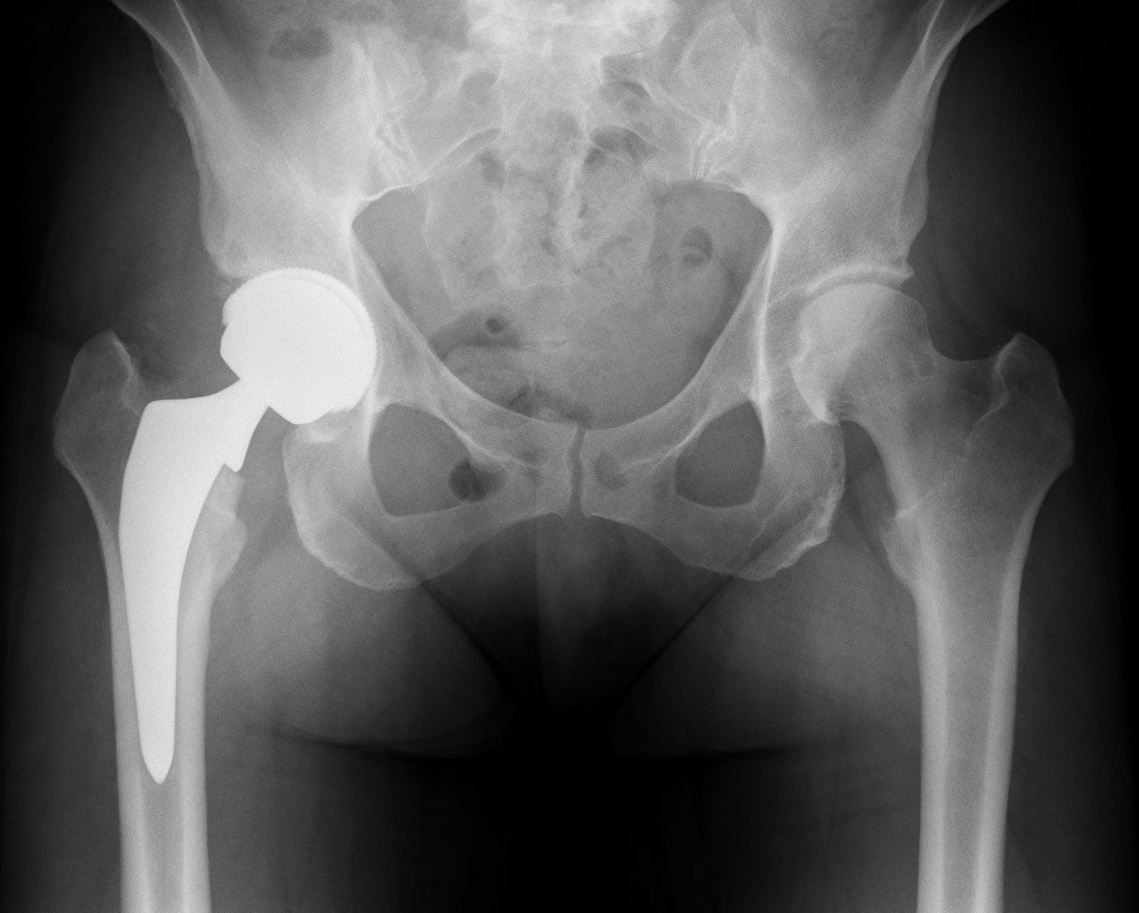

Hip Replacement

Hip replacement involves removing the damaged ball-and-socket joint of the hip and replacing it with artificial components to relieve pain and improve mobility. It is commonly performed for severe arthritis or joint damage that doesn’t respond to other treatments.